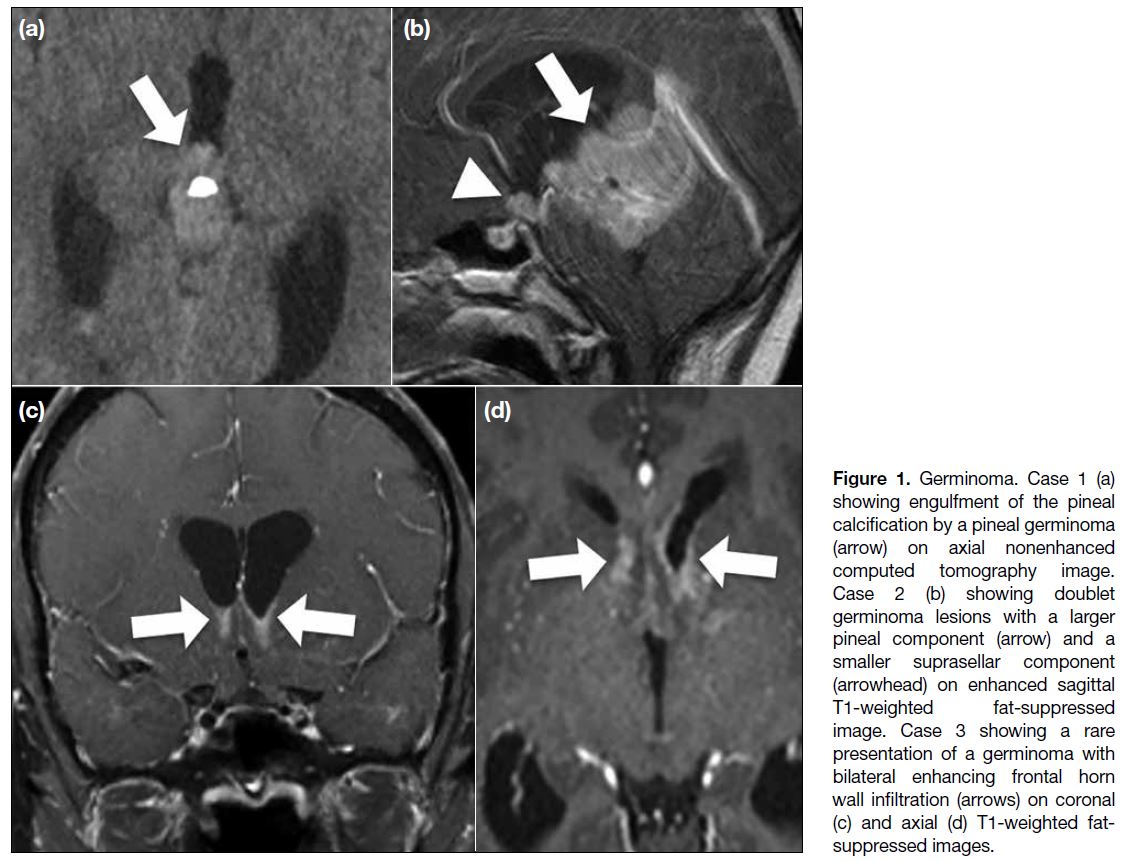

Computed tomography (CT) of the head seldom shows

calcification of the germinoma, but when located in

the pineal region, it can enlarge and engulf the pineal

calcification. In magnetic resonance imaging (MRI),

germinoma usually presents as iso- to hyperintense to

grey matter on T1-weighted and T2-weighted images,

with marked enhancement and cyst formation, and

hydrocephalus, as well as water restriction on diffusion-weighted imaging (DWI). Dissemination via the CSF and

invasion of adjacent brain parenchyma also commonly

occur.[3] [4] Because of the risk of CSF seeding, imaging

evaluation should include the entire neuroaxis; however,

even with extensive involvement, the prognosis of

germinomas is good because of the radiosensitive nature

of these tumours.[3] The prognosis of teratoma varies,

depending on the histological findings. Some clues to

the diagnosis of germinoma have been proposed, such

as engulfment of the pineal calcification and bifocal

involvement with normal alpha-fetoprotein level in the

serum and CSF. Nonetheless, surgical confirmation

is usually required.[3] [4] In our cases, there are typical

instances of engulfment of the pineal calcification,

doublet lesions, and also infiltrative lesions involving

both frontal lateral ventricular walls (Figure 1). However,

nongerminomatous GCTs can also demonstrate bifocal

involvement.[1] [2]

Figure 1. Germinoma. Case 1 (a)

showing engulfment of the pineal

calcification by a pineal germinoma

(arrow) on axial nonenhanced

computed tomography image.

Case 2 (b) showing doublet

germinoma lesions with a larger

pineal component (arrow) and a

smaller suprasellar component

(arrowhead) on enhanced sagittal

T1-weighted fat-suppressed

image. Case 3 showing a rare

presentation of a germinoma with

bilateral enhancing frontal horn

wall infiltration (arrows) on coronal

(c) and axial (d) T1-weighted fat-suppressed

images.